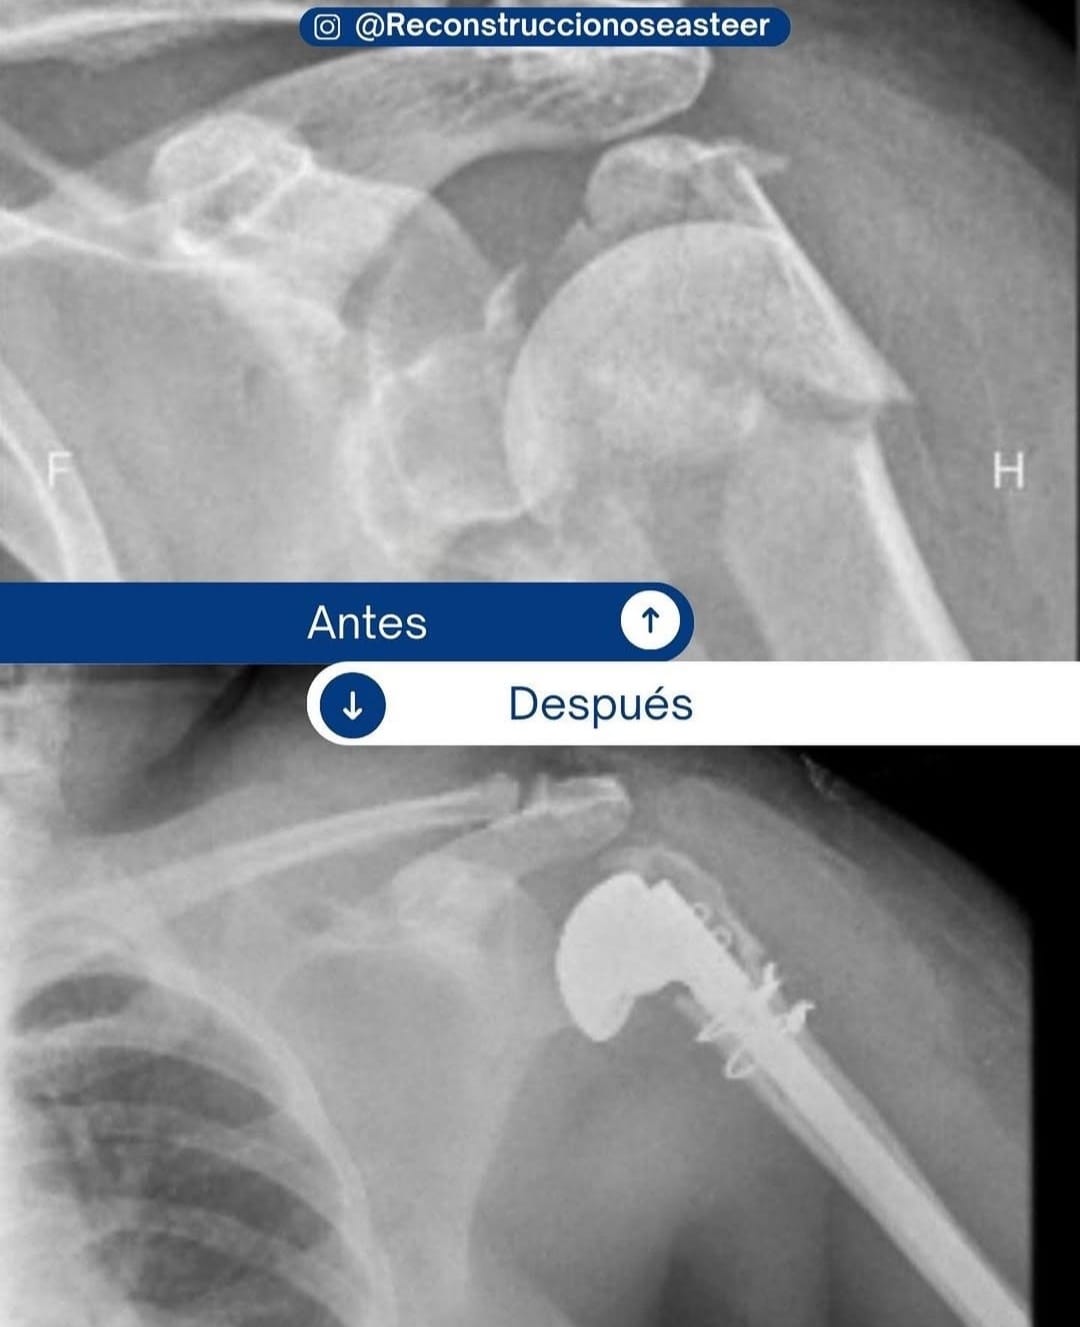

• Cirugía ortopédica reconstructiva

CASOS